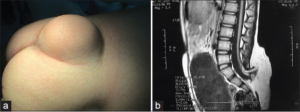

Липома на спине — фото

Хордома крестца

Диагностика хордомы крестца

Диагноз ставится на основании результатов КТ, МРТ, рентгенографии и биопсии. На снимках отчетливо видны дефекты костной ткани в виде перегородок.